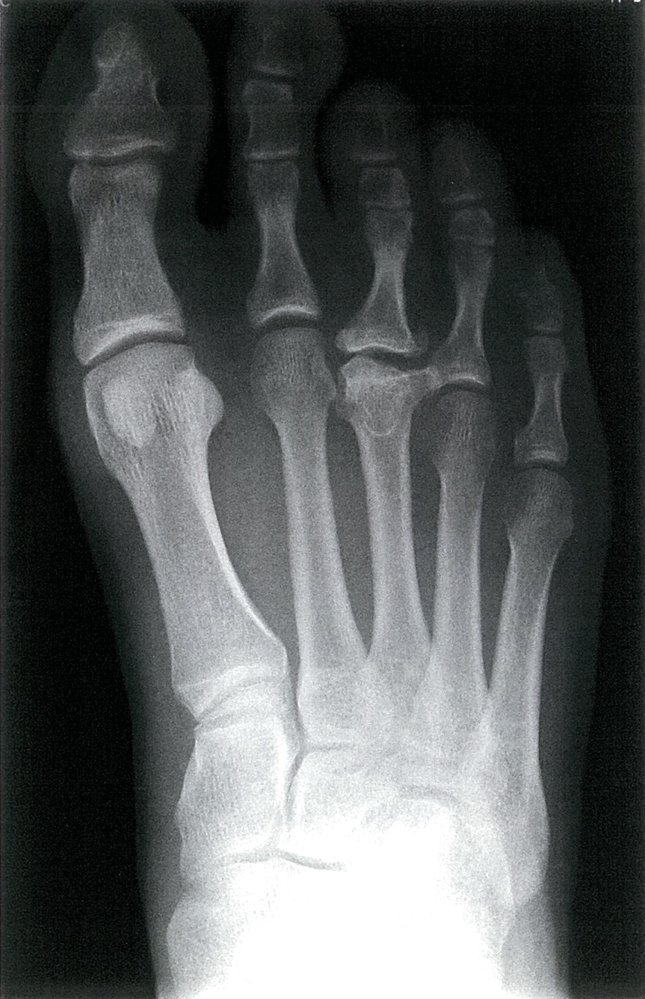

Freiberg disease

• Metatarsal head (most often II, but also III–V)

• Age of onset: 10–18 years

• ♀ > ♂

• More common in children with a long metatarsal II

• Pain in the forefoot